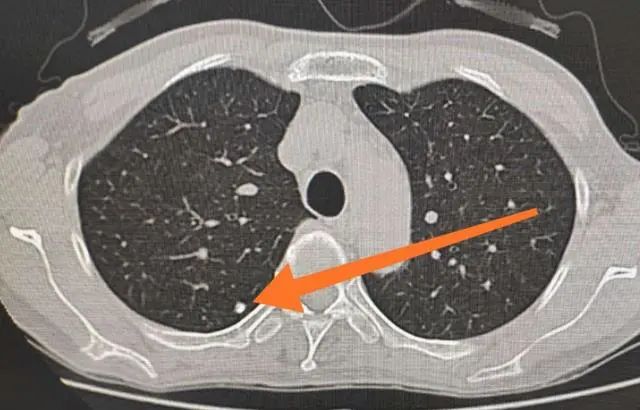

2、肺结节:

肺结节是指肺部内部密度增高的小结节,它并非特定疾病,而是一种影像学定义。

研究指出,在我国正常人群中,肺结节的体检发现率为20%~40%,其中90%的肺结节是良性的。若肺结节确诊为良性,一般无需手术治疗,只需进行常规随访。然而,如果初次检查时发现结节直径超过1厘米且被评估为高风险结节,存在较大的肺癌可能性时,可考虑及时进行外科手术切除。